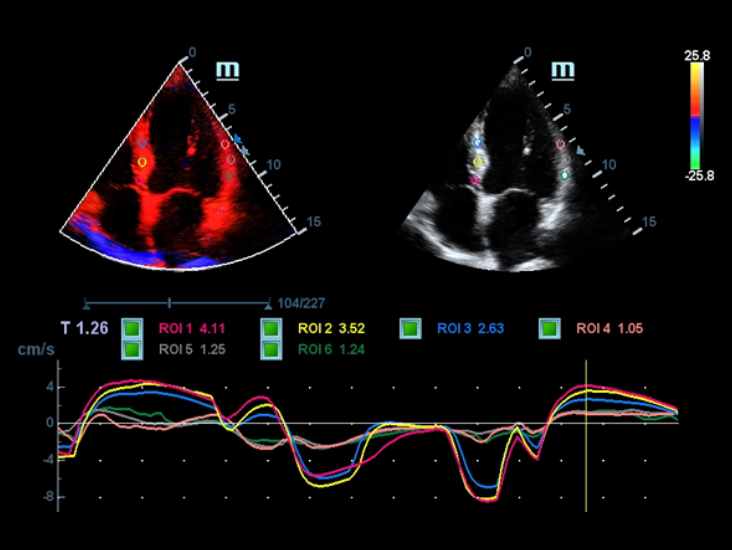

??? ?? ? ?? ???

???? ?? ??: ??? ?? ?? ??

?? ??? ????? ??????? ???? ?? ??? ?????? Full HD ??? ?? DC-40? ?? ?? ??? ??? ??????.

- iClear(??? ?? ?? ??)

- PSH(??? ??? ??)

- iBeam: ?? ?? ?? ??

???? ????? ???: ???? ?? ??

Full HD ??? ?? DC-40? ???? ????? ???? ??? ?? ???? ??? ?? ?? ??? ???? ??? ?? ???? ??? ?? ??? ?????.